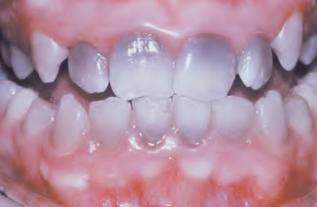

Gingival Cyst of the newborn | dental lamina rest | 新生兒上顎牙齦 ![]() |

- | 管腔內含有角質碎屑(keratinaceous debris) ![]() |